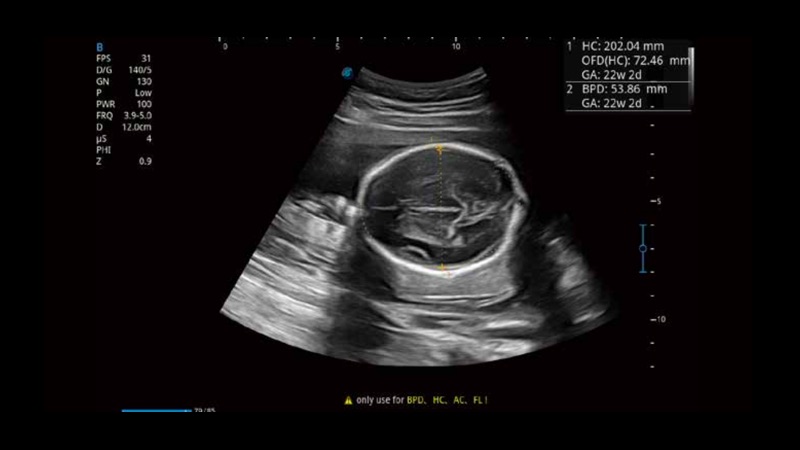

S-Fetus基于大数据深度学习算法,能够帮助您在产前筛查过程中智能识别胎儿标准切面、自动测量并录入报告。一个按键,即可智能、精准、高效地获取胎儿生理指标,极大简化您的产科检查操作。

可快速对产科扫查切面完成胎儿生理学参数的自动测量,减少操作者按键次数,大幅提升检查效率。

自动识别颈项透明层并获得NT值,为早孕胎儿畸形筛查提供有效测量工具,提高诊断效率和诊断信心。